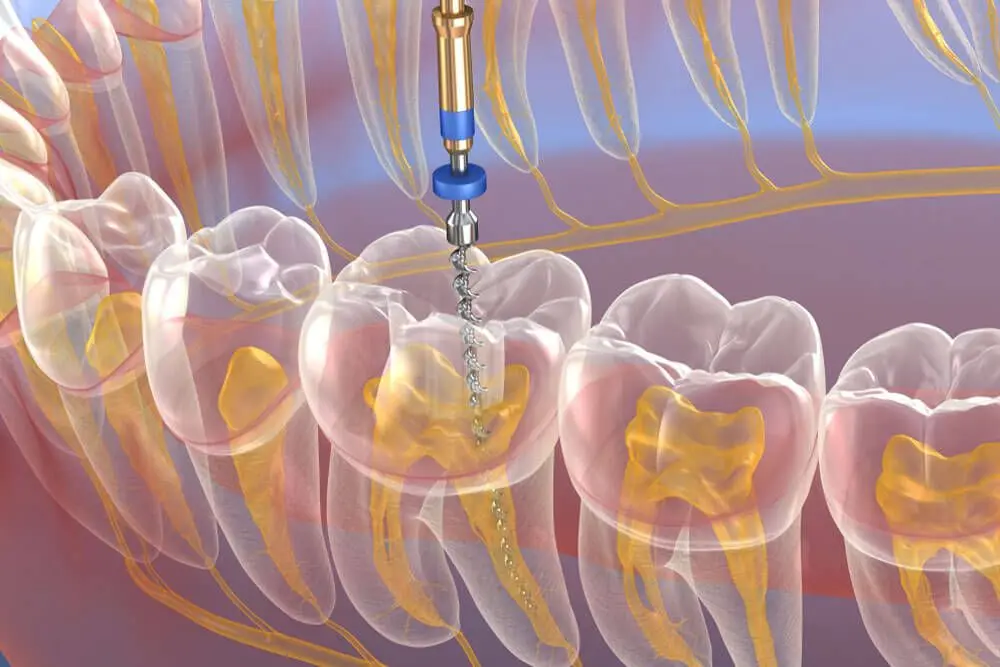

Root Canal Procedure

Our comprehensive root canal procedure involves several precise steps to ensure complete treatment and long-term success:

- Creation of small access opening to reach the root canals

- Removal of infected or damaged pulp tissue

- Cleaning, shaping, and disinfecting the root canal system

Advanced endodontic equipment for precise treatment